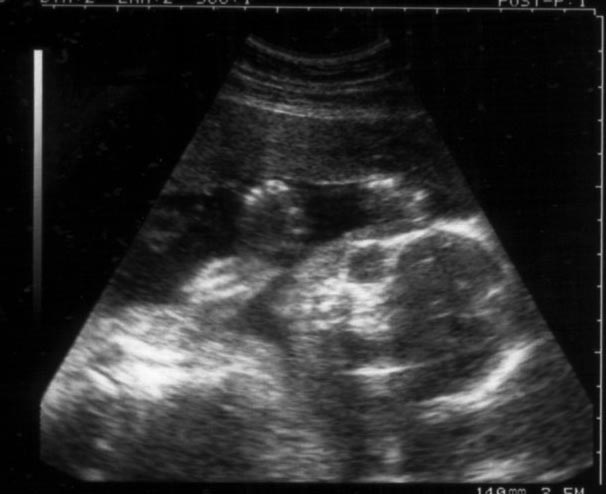

22wエコー 性別判定 22wのエコーです 男かもと言わましたが 次の 避妊 教えて Goo

赤ちゃんの性別判断をしていただきたいです エコー画像は22wです 病院で Yahoo 知恵袋

妊娠22週目 22w0d 6d のエコー写真とエピソード 妊娠6ヶ月 Cozre コズレ 子育てマガジン

性別判断お願いします 22wの赤ちゃんのおまたの写真です 性別は Yahoo 知恵袋